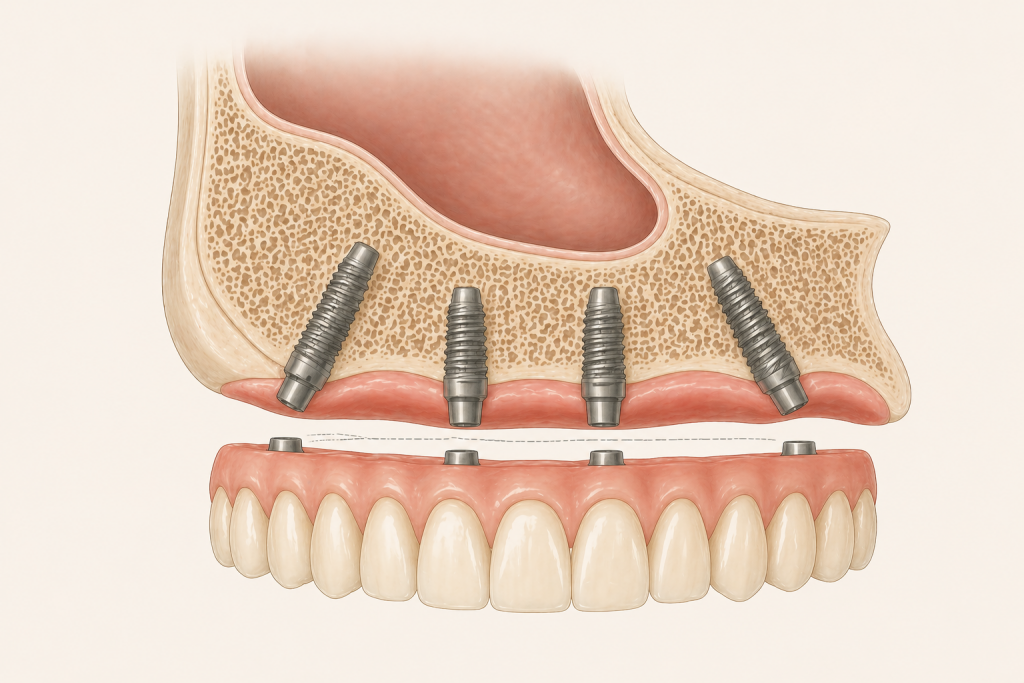

Perché a volte gli impianti sono inclinati

Non sempre l’osso è presente nelle zone ideali.

In alcune aree si riassorbe nel tempo, soprattutto dopo la perdita dei denti. Per questo motivo, in alcuni casi, gli impianti vengono inseriti con un’inclinazione specifica.

Non è una scelta casuale: serve per utilizzare al meglio l’osso disponibile, distribuire in modo equilibrato il carico masticatorio ed evitare, quando possibile, interventi più invasivi.